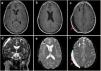

Presentamos el caso de un varón de 38 años remitido a nuestro servicio por la aparición brusca de diplopía con hemiparesia izquierda progresiva de 6 meses de evolución y caídas frecuentes. Tras realización de pruebas de imagen, se objetivan distintas lesiones intraaxiales y extraaxiales con diferente comportamiento radiológico decidiéndose un abordaje quirúrgico único para su exéresis. La anatomía patológica confirma cuatro variantes histológicas: meningioma (grado 1 y 2 [atípico]), subependimoma y cavernoma. Discutimos el papel teratogénico y efectos biológicos de las radiaciones ionizantes.

We present the case of a 38-year-old man referred to our department for a sudden diplopia with 6-month progressive left hemiparesis and frequent falls. After imaging tests, different intra and extraxial lesions with different radiological behavior were observed, performing a single surgical approach for their resection. The pathological anatomy confirms four histological variants: meningioma (grade 1 and 2 [atypical]), subependymoma, and cavernoma. We discuss the teratogenic role of ionizing radiation.